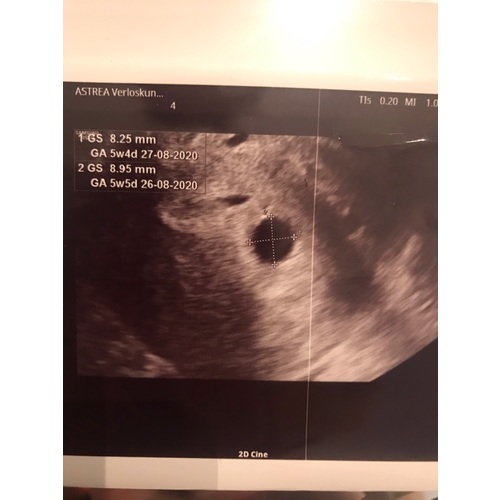

Ja klopt dat met die 2 weken kado snap k maar bedoel te zeggen officieel toen 5 weken dus dan kan zo zijn niks zag lees dat vaker vrouwen tot de 6 weken niks zagen dan alleen vruchtzak en zij zij grof ja miskraam vind eg nie kunnen terwel t kan kloppen kan zeker fout zijn maar t is zo ingewikkeld kijk de echo

Ik begrijp je verhaal denk ik...

Gynaecoloog zegt dat je 8 weken bent en een miskraam hebt omdat ze niks ziet.

Jij denkt dat je 6 weken bent (berekend vanuit ovulatie) en je hebt vaker gehoord dat je met 6 weken nog niks ziet...

Is dit een beetje de samenvatting?

Jaaa ☺️klopt helemaal was zelfs minder toen 24 dec echo had

Kan moeilijk verworden maar presies wat jij zegt

Als je 24 december je echo had was je op die moment 6 weken zwanger geteld van de 1ste dag van je laatste menstruatie op 12november. Ok je bent in werkelijkheid niet zwanger op 12 november maar je zwangerschap begint van die dag te tellen en daarom zegt de gynaecoloog wss dat je toen zwanger was, wss gewoon miscommunicatie. Als je op 6weken dus 24 december je echo had dan kan het idd zijn dat je enkel die ring ziet, hangt er een beetje vanaf wanneer je vruchtje is gaan innestelen en daardoor je aantal weken dus iets lager ligt, dus zou me daar geen zorgen inmaken en gewoon je volgende echo afwachten daar gaat normaal al veel meer te zien zijn. Wel bod van je gynaecoloog dat die onmiddellijk zegt dat het een miskraam is terwijl het nu nog alle kanten op kan

Ik snap dat je dacht pas 6 weken zwanger te zijn, en de gynaecoloog is ook erg bot geweest. Maar je was gewoon 8 weken zwanger. Die twee weken extra moet je echt gewoon meetellen. Als de gyn een echo maakt met 8 weken is dat idd 6 weken sinds je bevruchting maar zou je echt meer moeten zien dan alleen een ring. Het kan natuurlijk een latere innesteling zijn geweest maar alle metingen die een gyn of de echo apparatuur maakt zijn altijd incl die twee weken extra.